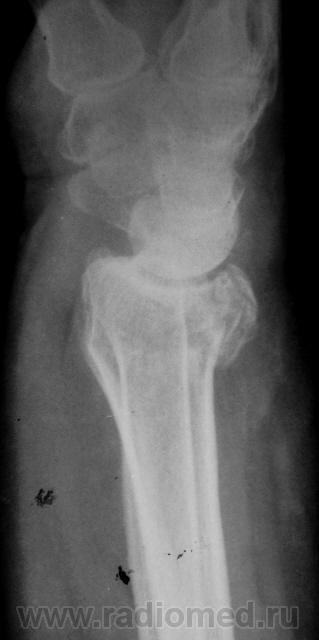

Травма. Пациент направлен на рентгенографию лучезапястного сустава.

луча в типичном месте. А вот шиловидный отросток похоже тоже сломался?